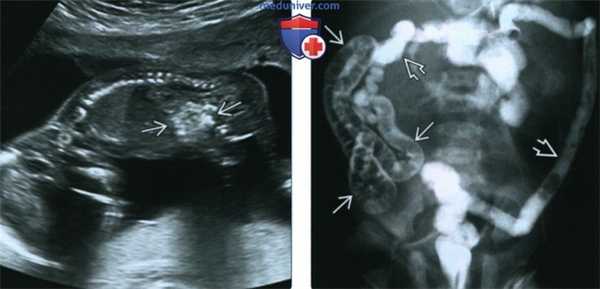

(Слева) УЗИ в III триместре. Лицо плода с СКДЛ. Определяются тонкие губы, вытянутый губной желобок впалая нижняя челюсть, а также дефект конечности.

(Справа) Клиническая фотография новорожденного с СКДЛ. Отмечаются некоторые характерные признаки заболевания, включая длинные ресницы тонкие губы и вытянутый губной желобок. (Слева) УЗИ плода во II триместре, фронтальная плоскость. СКДЛ. Визуализируется правосторонняя диафрагмальная грыжа, печень находится в полости грудной клетки. Наличие диафрагмальной грыжи на фоне СКДЛ связано с крайне неблагоприятным прогнозом.

(Справа) Тот же случай. Фотография, полученная во время посмертного исследования. Определяется крупная правосторонняя ВДГ, печень занимает практически всю правую половину грудной клетки. Наличие ВДГ в сочетании с пороками развития конечностей позволяет заподозрить СКДЛ. (Слева) УЗИ плода в 14 нед. Патологические находки, позволяющие заподозрить диафрагмальную грыжу: дно желудка находится в грудной клетке, сердце смещено к левой стенке грудной клетки. Смещение желудка кзади позволяет предположить, что печень также находится в полости грудной клетки. Позднее у плода диагностирован СКДЛ.